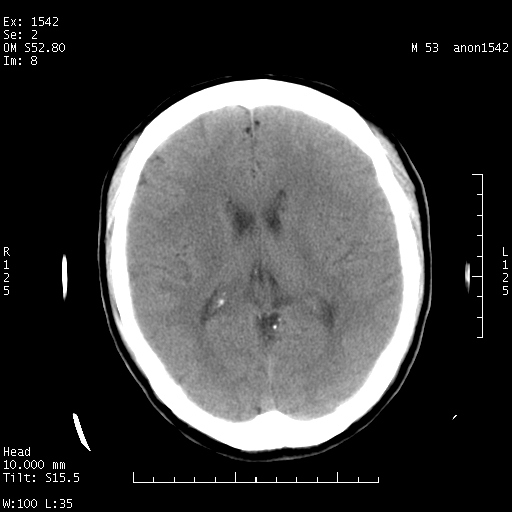

左侧鞍旁不规则低密度,此区域和侧脑室有液平。若无外伤史。考虑左侧鞍旁表皮样囊肿自发破溃。

鞍旁颞叶低密度灶.其中散在空气影.还有侧脑室.是否考虑脑脓肿(请提供病史情况)

此图像一定有创伤史才对,病史对明确判断很重要

楼主应该把病史传好,有没有发热病史或是外伤病史。